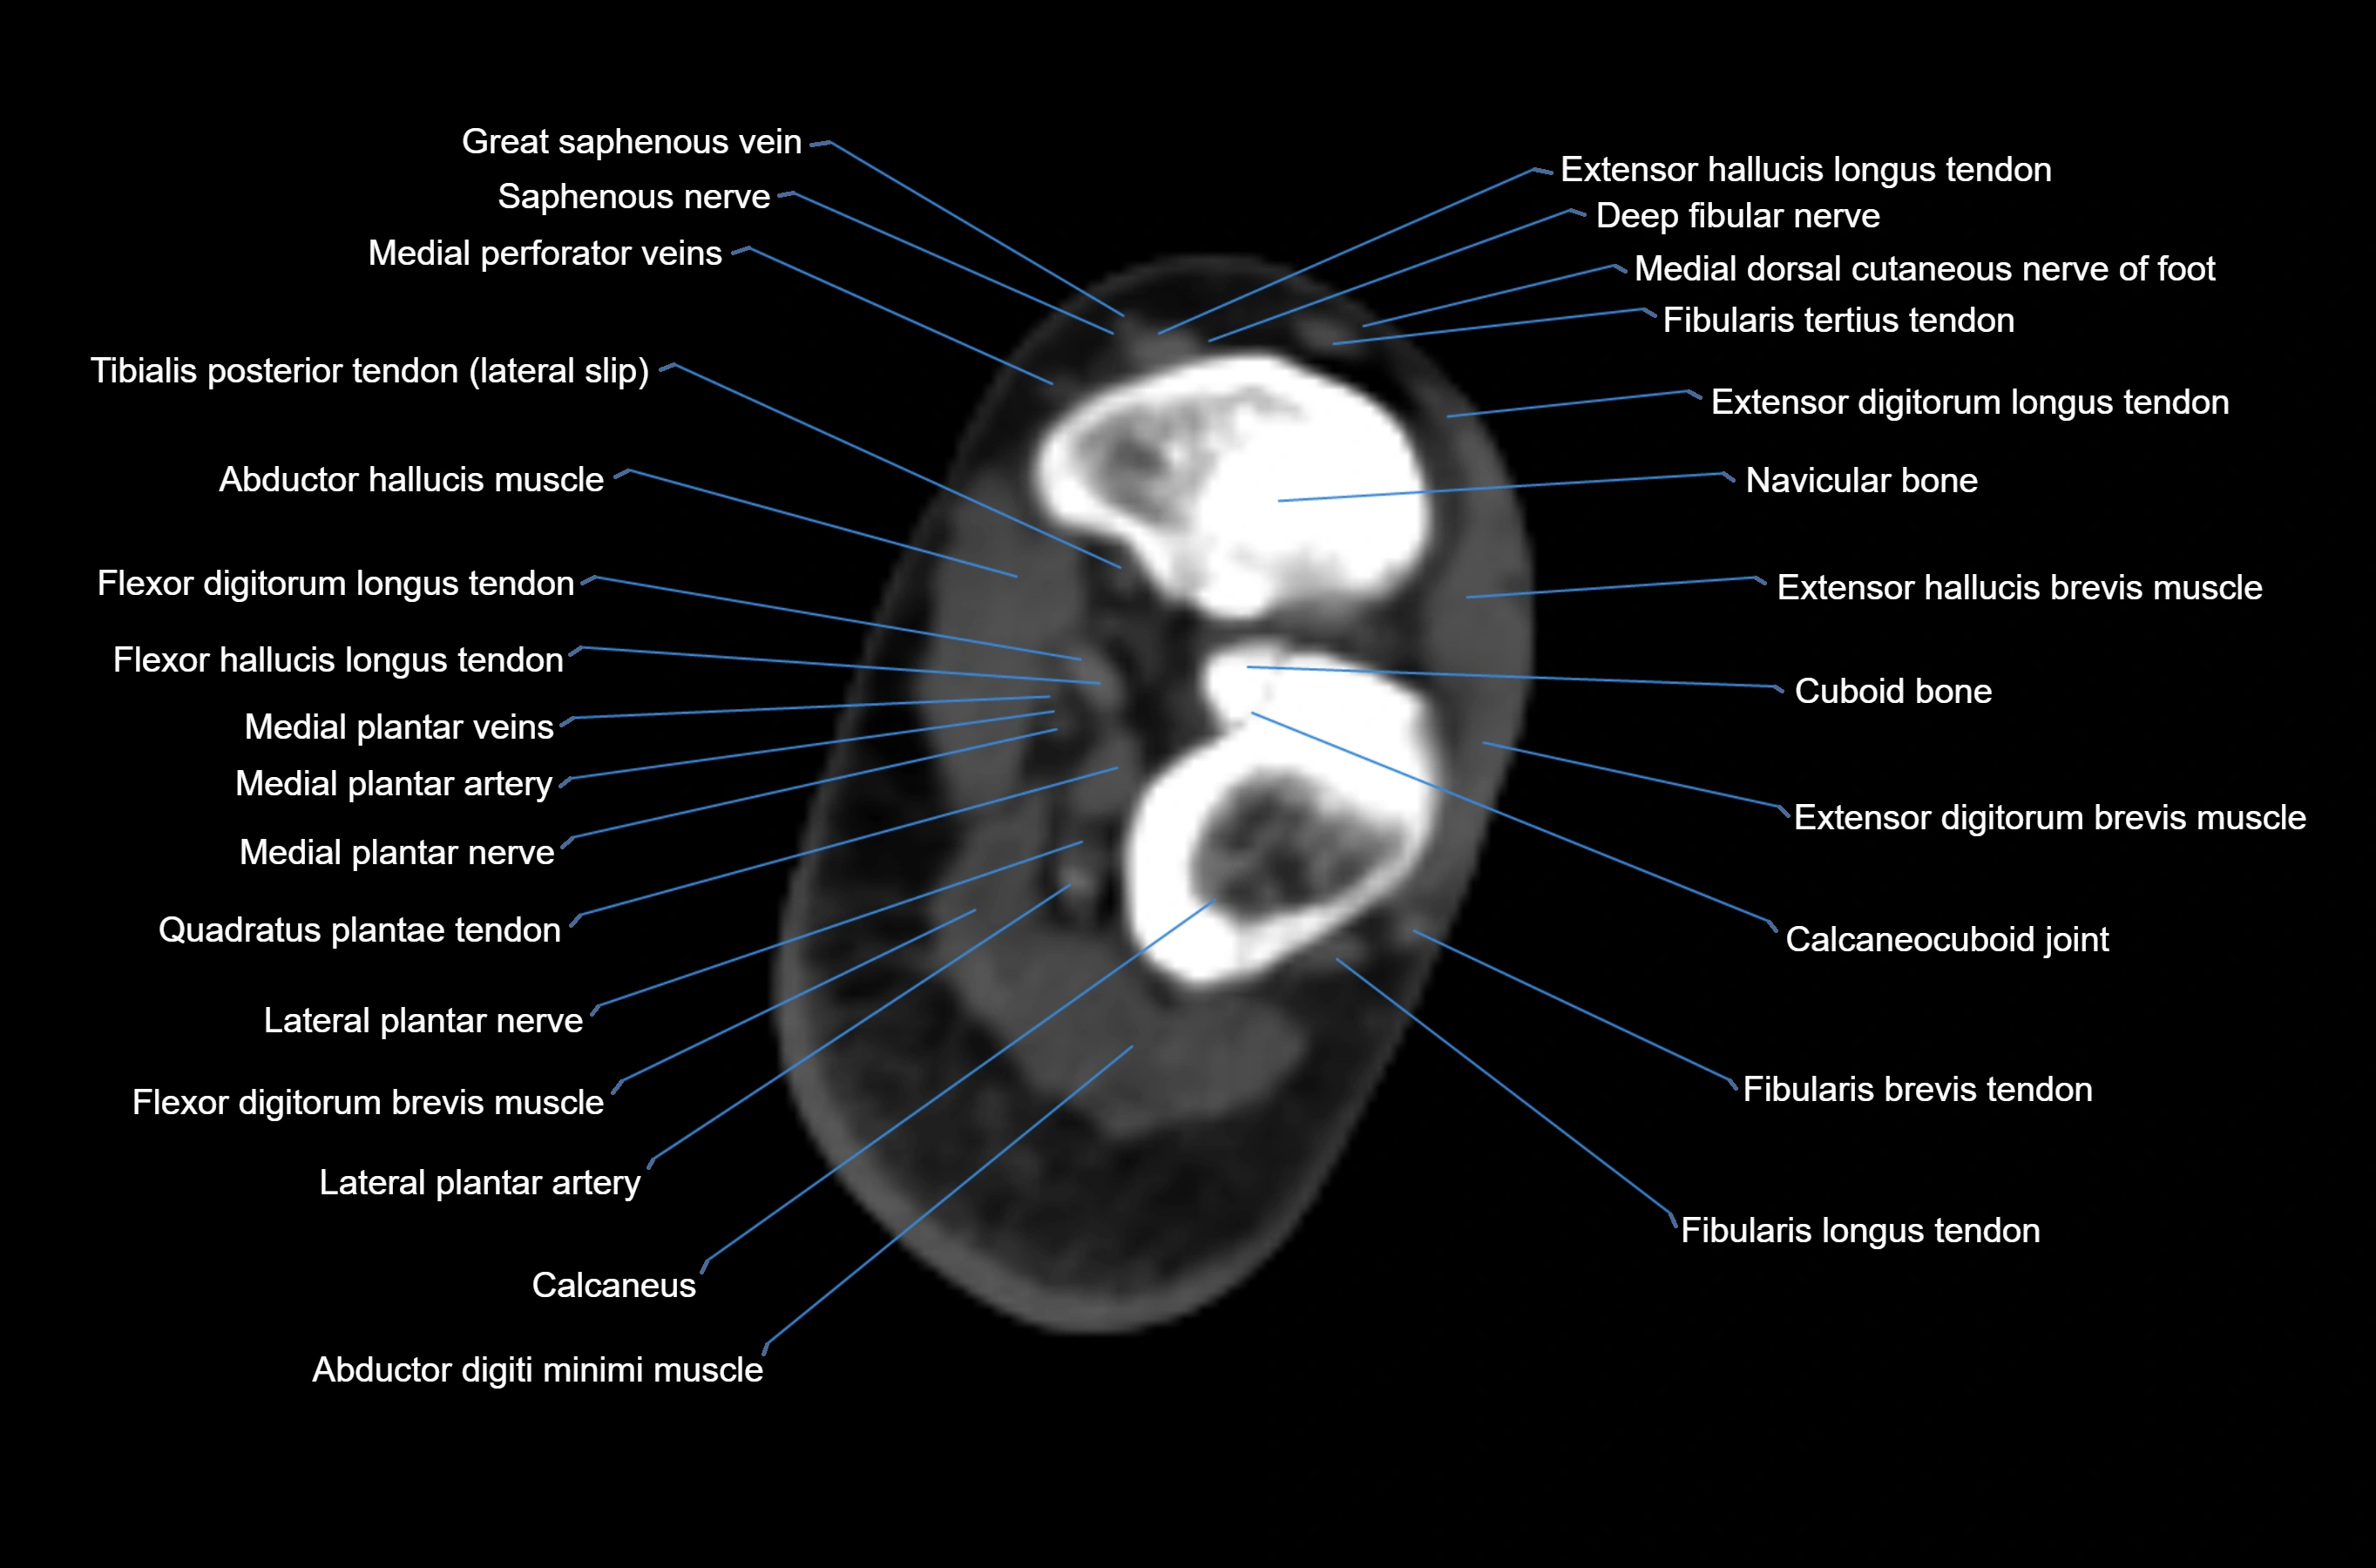

MRI image

CT image